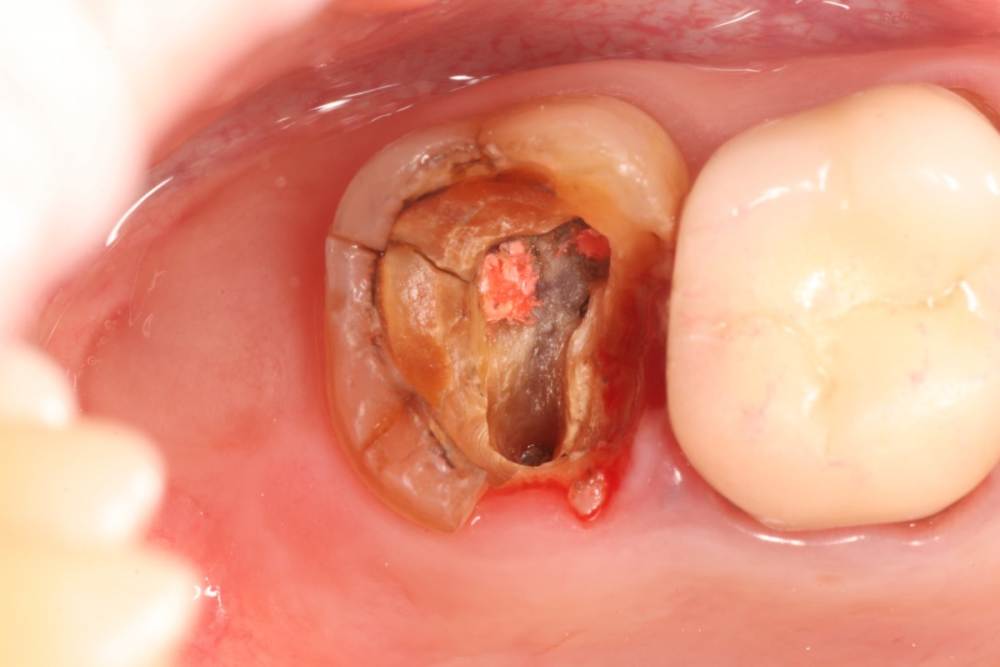

Complient Опубликовано 16 ноября, 2021 Поделиться Опубликовано 16 ноября, 2021 (изменено) Добрый день, буду признателен за мнения на мой случай. Ситуация: - на корне 6-го (под коронкой) воспаление (видно на фото КТ снимка) - на 7-м под вкладкой оказались сильные разрушения (видно на фото) Предлагают удалить 26,27,28 разом, чтобы потом, как заживет, ставить 2 импланта. Интересует мнение сообщества: 1) Есть ли риски удалять 8-ку сразу вместе с 6 и 7? Или лучше позже отдельно? 2) Нужен ли тут синус-лифтинг? 3) Через сколько после удаления можно приступать к имплантам/синус-лифтингу? Изменено 16 ноября, 2021 пользователем Complient Ссылка на комментарий